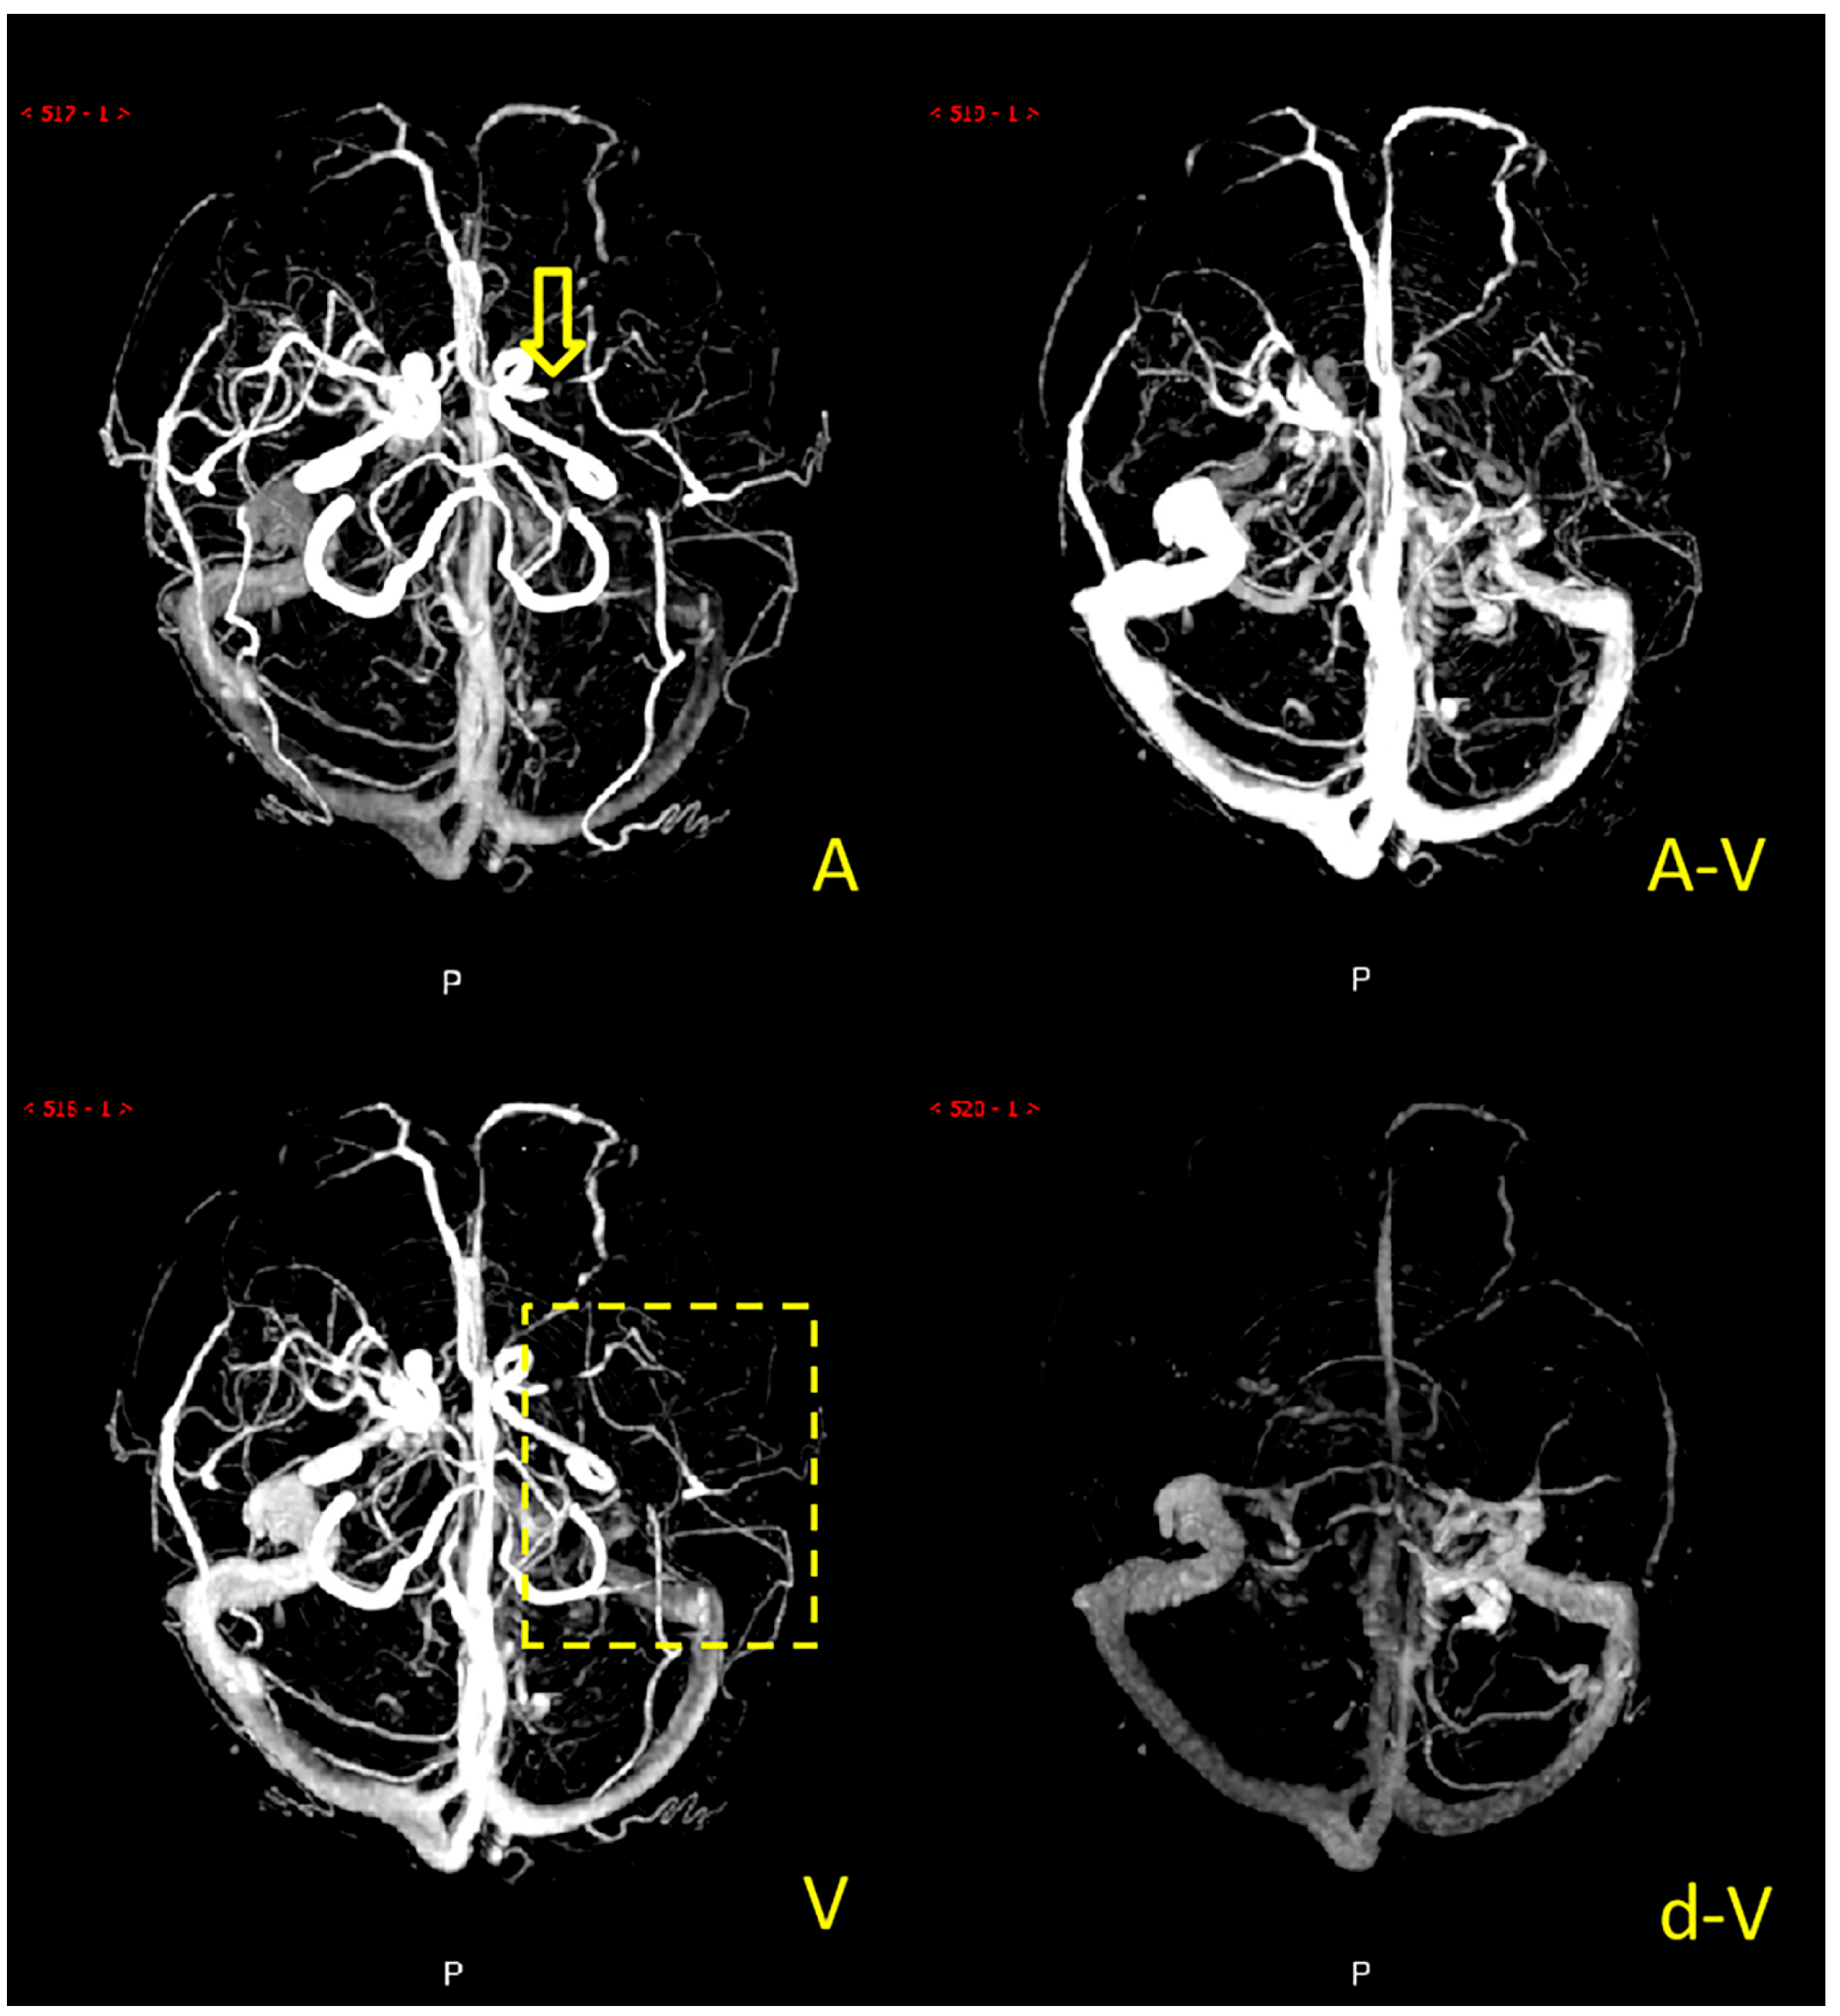

Collateral circulation grading was performed using a modified ASITN/SIR (American Society of Interventional and Therapeutic Neuroradiology/Society of Interventional Radiology) collateral grading scale based on dynamic multi-period CTA [5,14,15]. The scale consists of 5 levels: level 0 indicates no or few collateral branches in the ischemic area at any stage; level 1 is partial collateral circulation until the late venous phase; level 2 is partial collateral circulation in the ischemic area before the venous phase; level 3 is complete collateral circulation formation in the ischemic area in the late venous phase, and level 4 is total collateral circulation before the venous phase. Grades 0 to 2 were defined as poor collateral circulation (Figure 2), while grades 3 to 4 were defined as good collateral circulation (Figure 3). We marked patients as having good or poor collateral circulation according to each patient’s dynamic CTA collateral grading. Two experienced neuroradiologists performed the scoring, and they negotiated a solution if they had a different opinion. The scoring process was blinded to the clinical data.

Figure 3. Example of a patient with good collateral circulation. Note: the M1 segment of the right middle cerebral artery of the patient was occluded (the yellow arrow), and there were many collateral vessels in the blood supply area (the yellow dashed box) of the right middle cerebral artery in A (arterial phase), A-V (arteriovenous phase), V (venous phase), and d-V (venous late phase).